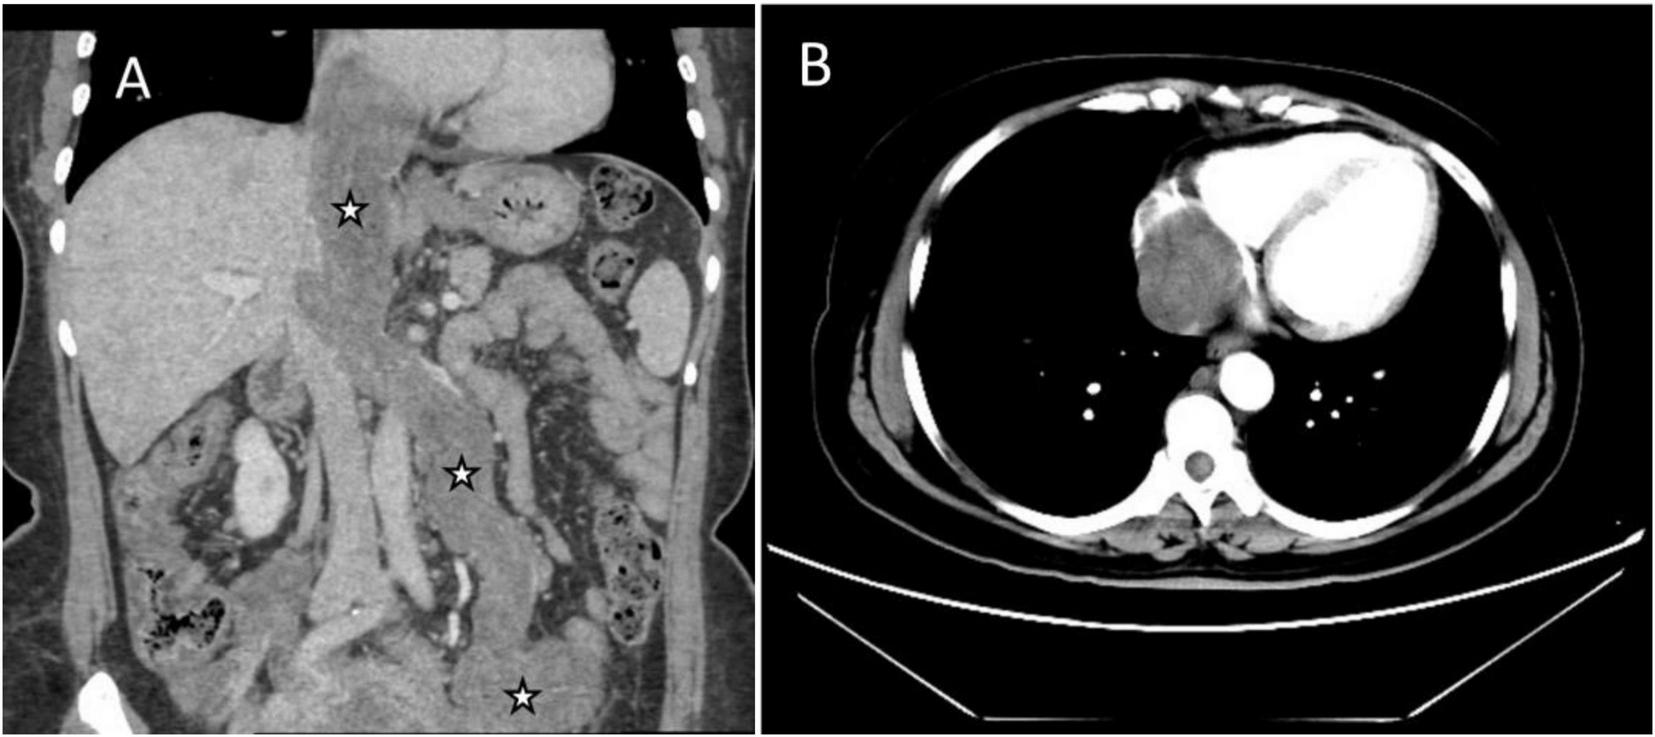

Abdominal enhanced computed tomography (CT) and inferior vena cava CT venography (CTV) demonstrated the presence of multiple soft tissue masses surrounding the uterus, extending from the left ovarian vein, left renal vein, and inferior vena cava to the right atrium (Figure 1). These masses exhibited slight enhancement. The second hepatic hilum was obstructed by the mass, resulting in a slender middle hepatic vein and a dilated accessory hepatic vein in the posterior right lobe. Additionally, the formation of communicating branches between the hepatic veins was observed (Figure 2).

FIGURE 1

Images of the mass in inferior vena cava (IVC) and right atrium on enhanced CT. (A) Coronal image showed multiple soft tissue masses surrounding the uterus, extending from the left ovarian vein, left renal vein, and IVC to the right atrium (asterisks). (B) Transverse section showed that the lesion occupies almost the entire right atrium.